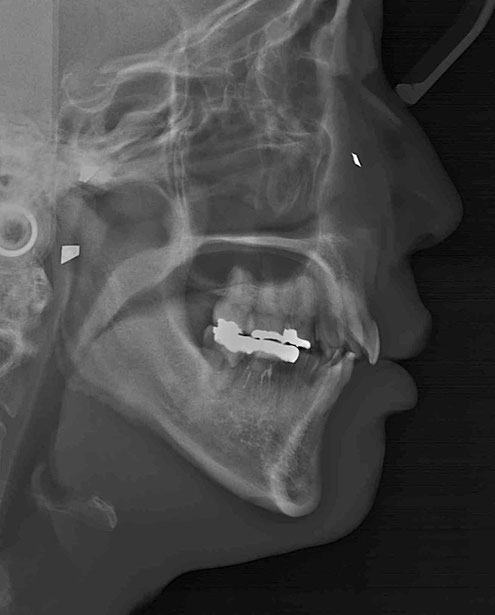

今回のケース

矯正治療後に奥歯の歯ぐきが2~3ミリ退縮。

その結果、露出した根の一部が虫歯になっていました。

治療のポイントは“順番”

このような場合、

✔ 虫歯の除去

✔ 歯ぐきの再生治療

を組み合わせて行います。

治療後の変化

再生治療により、

2~3ミリ下がっていた歯ぐきが回復。

歯の長さが自然なバランスに戻り、

厚みのある丈夫な歯ぐきが再建されました。

奥歯6本の再生治療を行ったケースでは、